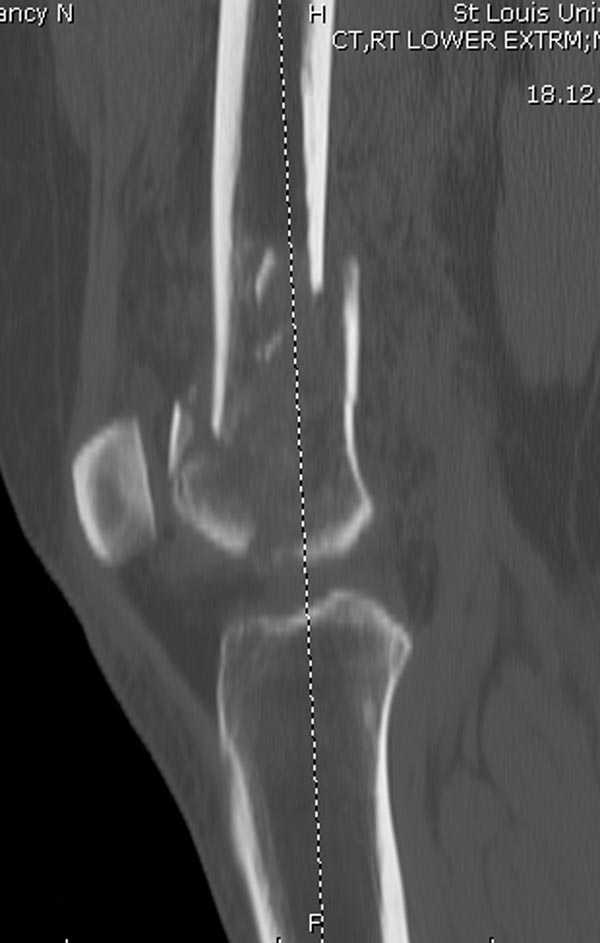

Бесспорно, предлагаемый ретроградный метод имеет свои преимущества, но имеется опасность при манипуляции интрамедуллярным гвоздем расколоть мыщелки.

Раскол можно предупредить шурупами, но короткий дистальный фрагмент навряд ли позволит добиться адекватной стабильности конструкции. Стандартные гвозди не рассчитаны для таких переломов, и если все таки желаете провести фиксацию гвоздем, тогда надо заказывать специальный custom made nail т.е. с расширенной возможностью дистальной блокировки.

Поэтому такие меж и над- мыщелковые переломы более предпочтительным считается фиксировать мыщелковыми пластинами